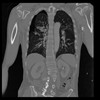

29 CUERPO,CE,Coronal,3.000,CUERPO,Coronal,